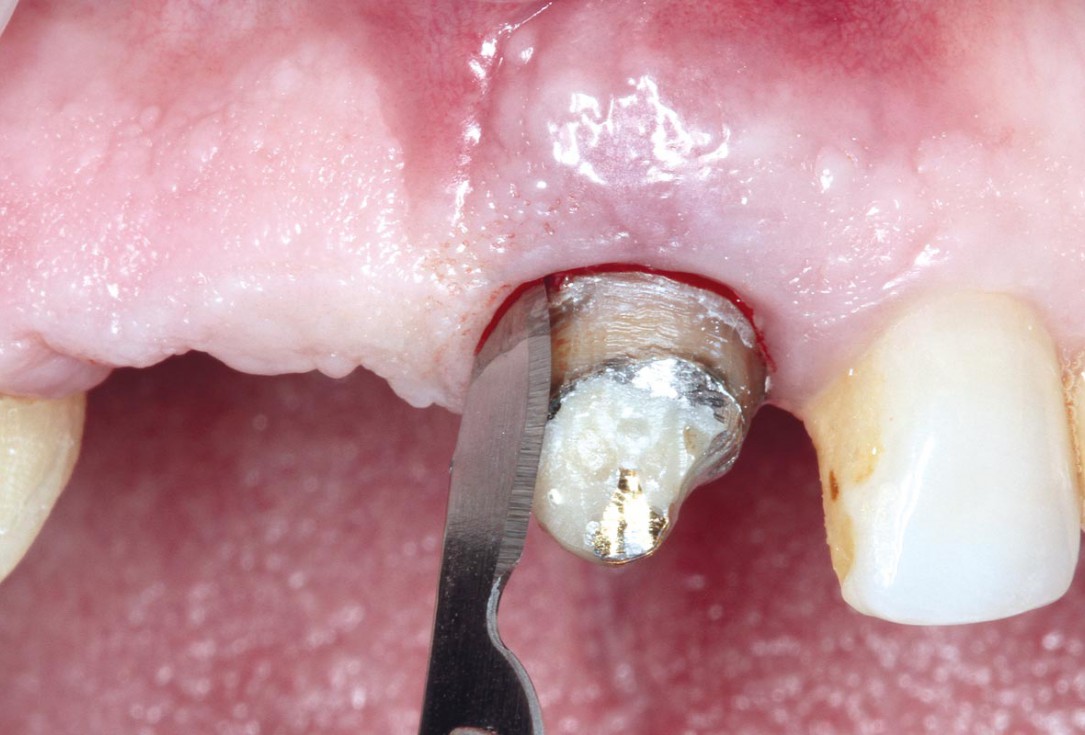

15/17 - Implant placement 6 months post-operative. Prosthetic restoration.

Socket preservation using cerabone® and Straumann® Emdogain® - Dr. S. Pelekanos